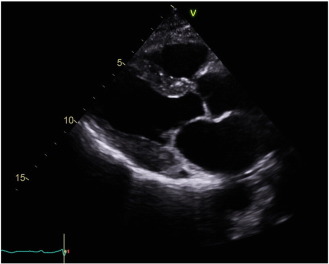

We have previously reported that with hematologic remission after PBSCT, some patients with cardiac amyloidosis had regression of the cardiac anatomical and functional manifestations, as assessed by echocardiography (see Fig. B.2) [18]. There are case reports and series in the literature suggesting that regression of CMR changes occur also, with faint residual enhancement described following stem cell treatment [19]; [20]; [21] ;  [22]. Until recently, CMR had not been a routine component of our cardiac amyloidosis work-up, due to a lack of funding in the Australian private health care system. The diagnosis of cardiac amyloid does not require the use of CMR [23] but is certainly enhanced by this use of this technique [14]; [15]; [16] ;  [17].

Echocardiography suggested statistically significant regression in the cardiac amyloid process, similar to what had previously been reported [18]. Wall thickness significantly reduced, atrial size shrunk, and measures of diastolic function improved (see Fig. B.1 ;  Fig. B.2). The ejection fraction did not significantly change. Myocardial strain analysis at late follow-up suggested better global longitudinal strain in this highly selected group of survivors, than many cardiac amyloid studies have suggested (the global longitudinal strain was more negative than previously reported for cardiac amyloid patients) [13]; [25] ;  [26]. The mean global longitudinal strain was − 16%. The classical bulls-eye pattern of cardiac amyloidosis was only seen in 50% of these patients [13] ;  [26] (see Fig. B.3 and Table A.2). Strain had not been assessed before PBSCT for any of the patients in this study.

Repeat echocardiography on the day of the CMR at late follow-up confirmed that patients still had macroscopic regression of cardiac infiltration, based on the echocardiographic images. There was marked improvement in echocardiographic anatomical and functional parameters compared to the pre-PBSCT echocardiograms. The post-PBSCT echocardiograms showed near normal global longitudinal strain. The classical bulls-eye pattern of cardiac amyloidosis [13] was seen in 50% of these echocardiograms. The CMR scans in this study showed similar wall thicknesses to that shown on echocardiography, supporting the suggestion that disease regression can occur in cardiac amyloidosis.

Fig. B.2.

Post-PBSCT echocardiogram.